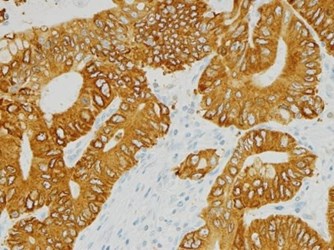

FGFR2 (fibroblast growth factor receptor 2)

FGFR2 is a receptor tyrosine kinase (RTK) that is responsible for mediating a number of intracellular processes culminating in cell growth and proliferation. Increased expression of FGFR2 protein has been observed in a number of human malignancies, including gastric, lung, ovarian, and breast cancers.